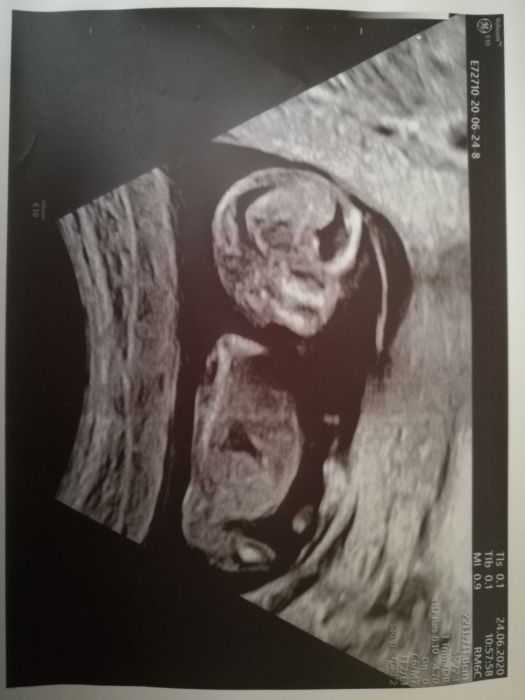

Ahoj holky, tak my dneska po kontrole a odchod s prukazkou. Zatim to vypadá, že jsme o 4 dny mladší, ale pry potvrdi až po screeningu ten máme 15.7. Mrně má 2.67cm podle doktorky se tam mrska o sto šest, takže jestli to bude živel jak malá, tak mi ty děti dostanou do Černovic. Jinak vše zatím ok a máme aj fotečku